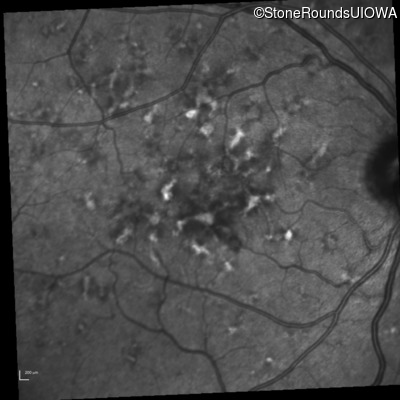

Fluorescein Angiography - Right - 20/40 +2 sc

Exemplar

Fluorescein Angiography - Left - 20/40 +1 sc